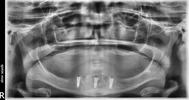

Implant tedavisi